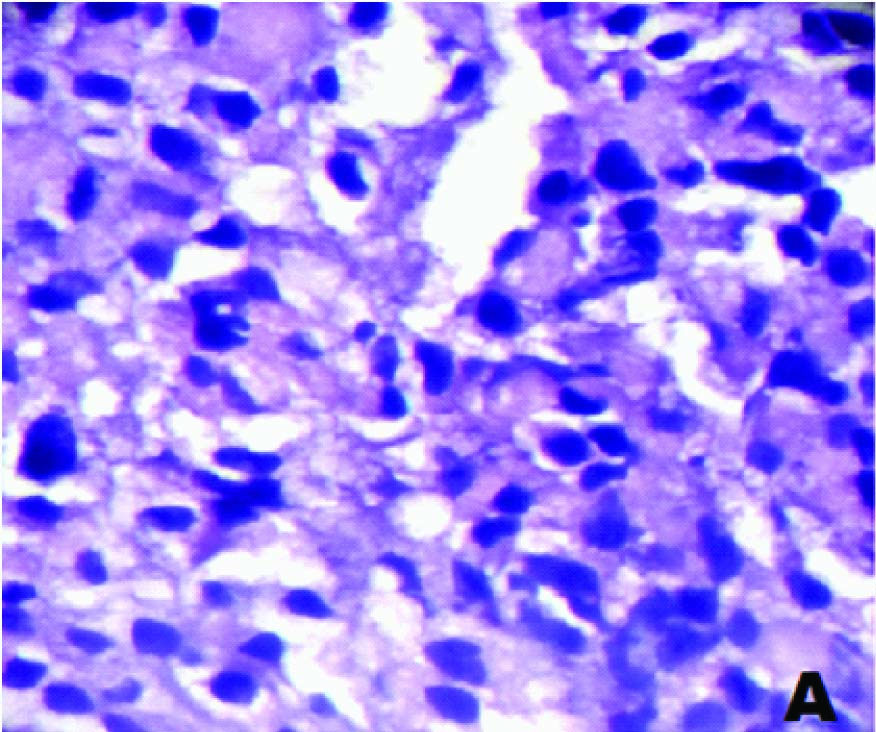

A 55-year-old male patient presented with pain abdomen and multiple skin nodules over the anterior abdominal wall and left cervical lymphadenopathy. On local examination, the abdominal skin nodules were firm to hard in consistency and the largest measured 3 x 2 cms. The left cervical lymph node was single, discrete and firm to hard in consistency. FNAC was performed on the abdominal skin nodules and the left cervical lymph node. FNAC smears studied from both the left cervical lymph node and the abdominal skin nodules showed similar cytological features. The smears were highly cellular and showed predominantly dispersed cell population of uniform tumour cells [Table/Fig-1a] in sheets, clusters, rosettes and tumour balls [Table/Fig-1b]. The cytoplasm was moderate, eosinophilic and granular. The nuclei were round to oval, with stippled chromatin and inconspicuous single prominent nucleolus [Table/Fig-1c]. Plenty of atypical mitoses were present [Table/Fig-1d]. In addition, many multinucleated giant cells and bizarre tumour cells were seen. Extracellular eosinophilic basement membrane- like material was also seen [Table/Fig-2a].

FNAC of cervical lymph node showing monomorphic tumour cells (MGG, ×1000)

Sections from the supraglottic growth revealed hyperplastic stratified squamous epithelium and a tumour in the subepithelium which was composed of monomorphic tumour cells arranged predominantly in diffuse sheets separated by fibrovascularseptae [Table/Fig-2b]. Occasional rosettes and trabecular patterns were observed. The tumour cells had moderate eosinophilic cytoplasm, round nuclei with fine chromatin and inconspicuous nucleoli. A few bi and multinucleated tumour giant cells were also seen. Foci of vascular invasion were seen.

Histopathology showing tumour cells separated by fibrovascular septa (H&E,×400)